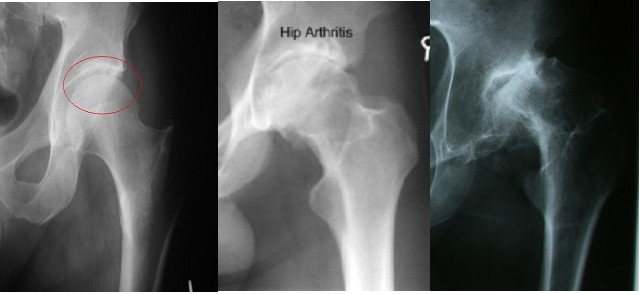

Standing x-rays of the hip joint will give a good assessment of remaining joint space and bone changes related to arthritis:

A simple x-ray should show changes of osteoarthritis. The x-ray findings classically include as joint space narrowing, subarticular sclerosis, osteophytes and degenerative cyst formation.